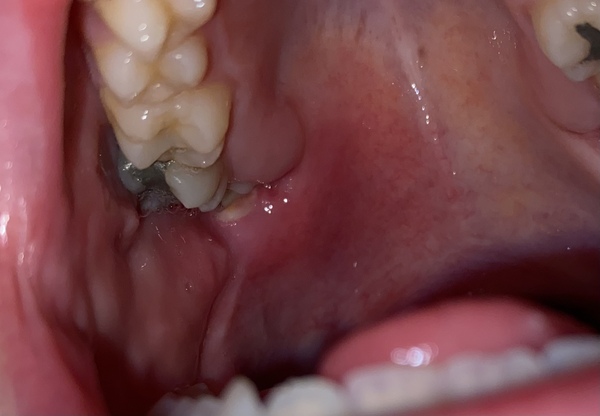

Ignore my gross teeth/filling. 🥺🥺

What do you think it could be? X

Just looks infected. Mine was the same but bottom. Mine was because the wisdom tooth is covered by gum so it just keeps getting infected despite good oral hygiene.